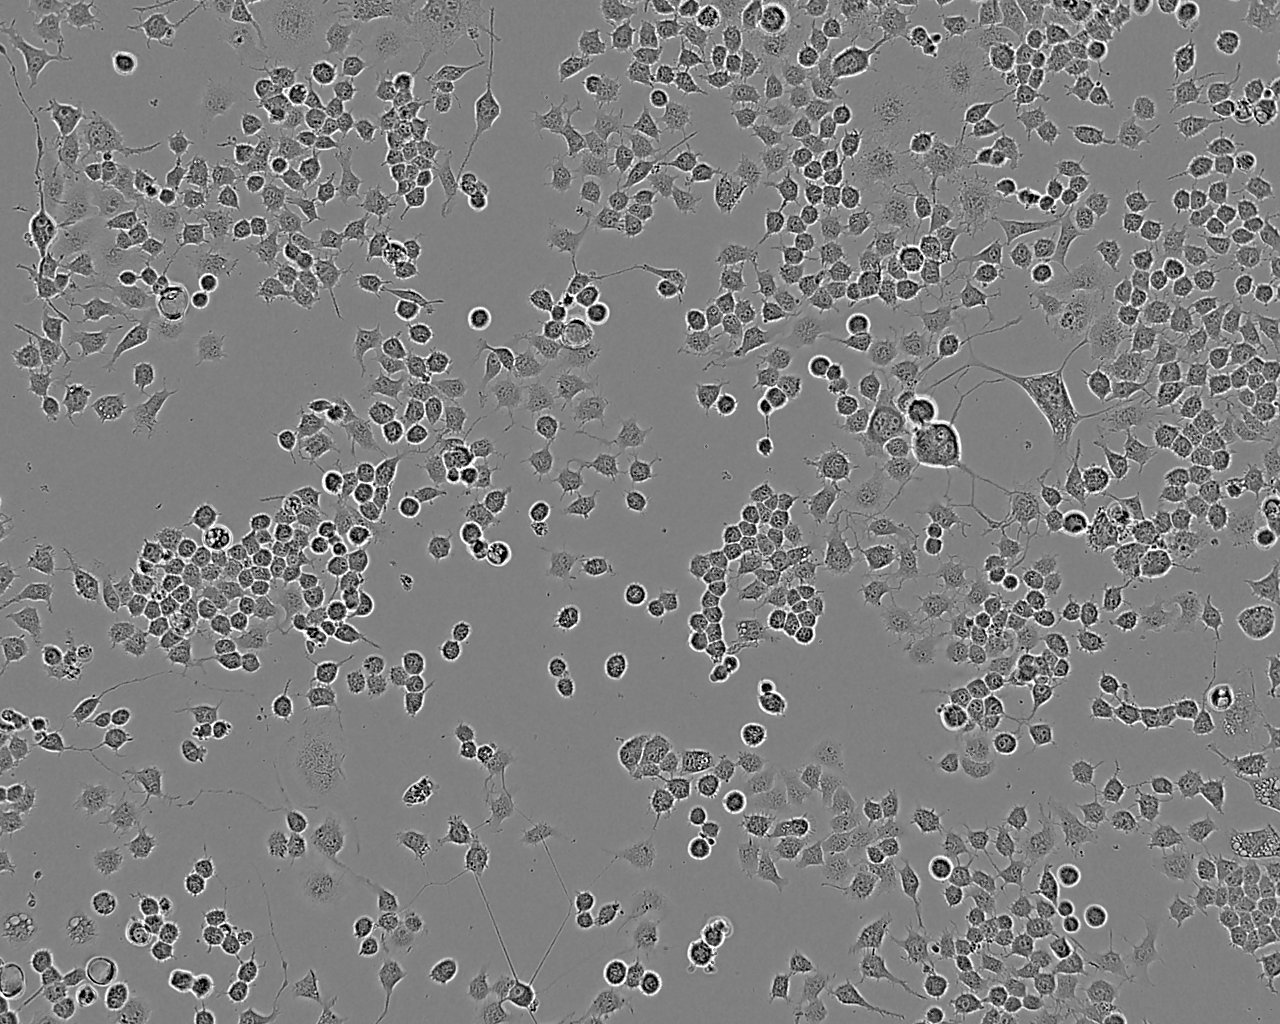

NCI-H1435细胞:人非小细胞肺癌细胞系

细胞形态:上皮细胞样

细胞生长:贴壁

细胞生长特性:贴壁生长,松散